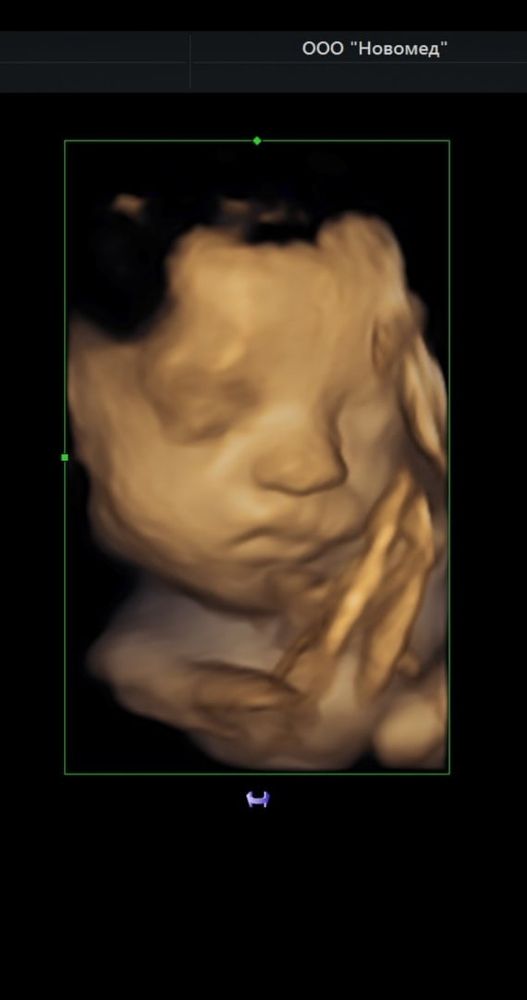

Да, очень. 30 недель, после рождения, 10,5 месяцев Изображение

Ой да, наша крошка родилась очень схожей с 3D 🥰